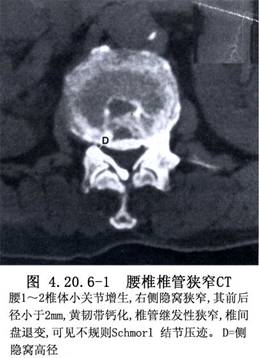

腰椎狭窄是老年常见病,致病因素复杂:有先天性椎管狭窄的因素,亦有因年龄的增长,椎骨、椎间盘变性,导致间盘突出,以及骨赘、骨嵴(bone ridge)形成等继发因素,造成马尾和神经根受压。临床表现主要是:腰腿痛、下肢麻木、无力,走路不稳和间歇性跛行(intermittend claudication)等。Sachs和Fraenkel(1900)报告1例背痛和神经源性间歇性跛行,经椎板切除而缓解。Verbies称此病为腰椎椎管狭窄。Schlesinger(1995)和Epstein(1992)先后提出侧隐窝狭窄(lateral recess stenosis)常与腰椎狭窄和腰椎间盘变性伴发。Javid等(1998)将这些病例情况称为腰椎狭窄或称变性性腰椎狭窄(degenerative lumbar stenosis)。近年来由于影像学检查的发展。多能清晰地显示病变的性质和范围而作出确切的诊断,但由于病变广泛,有的位置隐匿,以致手术难以彻底切除压迫物。一些作者大宗病例的统计分析,减压性椎板切除的疗效仅为2/3,伴有侧隐窝狭窄者疗效更差,需要行第二次手术者占15%左右。故病变的分析和手术操作仍待提高(图4.20.6-1)。